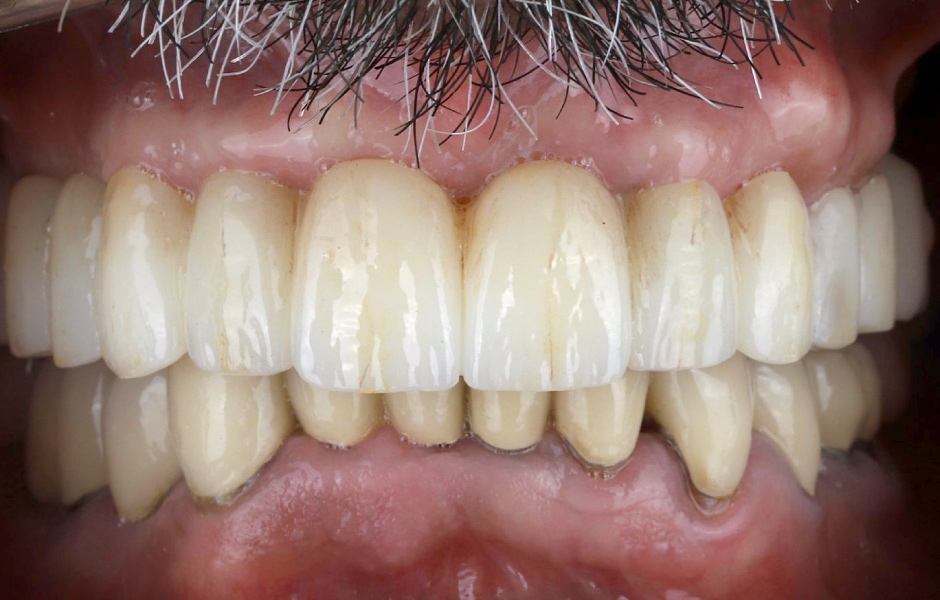

Definitivní náhrada byla nasazena a ověřena z hlediska estetiky, okluze a funkce (obr. 51–55). Panoramatický kontrolní snímek potvrdil, že všechny parametry protetického ošetření odpovídají očekávaným hodnotám (obr. 56).

Při kontrole po 18 měsících po dokončení ošetření bylo provedeno intraorální, extraorální a radiografické vyšetření. Nebyly zjištěny žádné patologické nálezy a výsledné parametry zůstaly stabilní (obr. 57–62).

Obr. 51

Obr. 52

Obr. 53

Obr. 54

Obr. 55